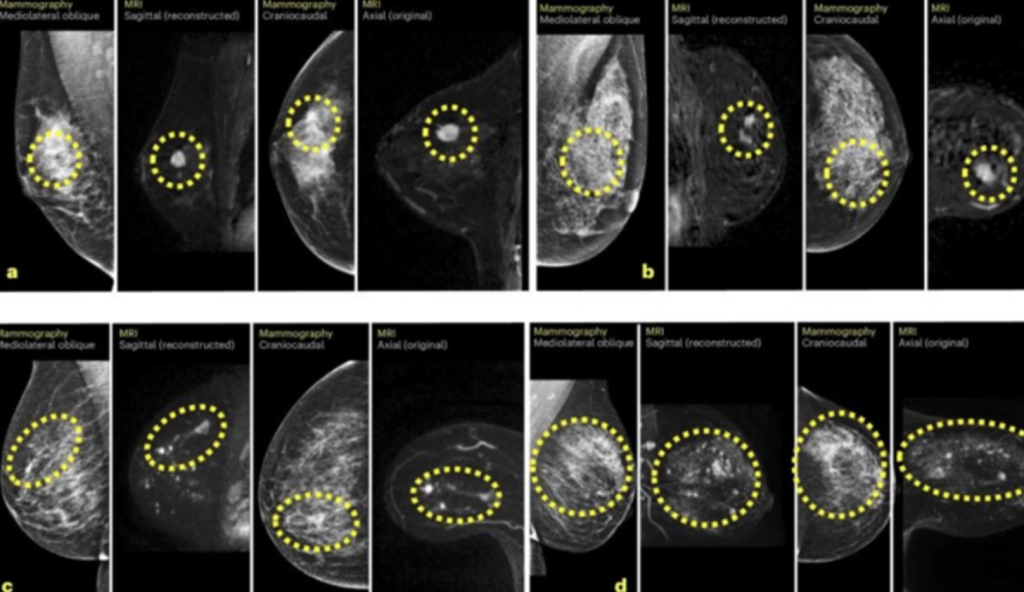

To bi kliničarima moglo omogućiti da pacijenticama s najvećim rizikom ponude i dodatna snimanja, poput magnetske rezonancije ili mamografije s kontrastom.